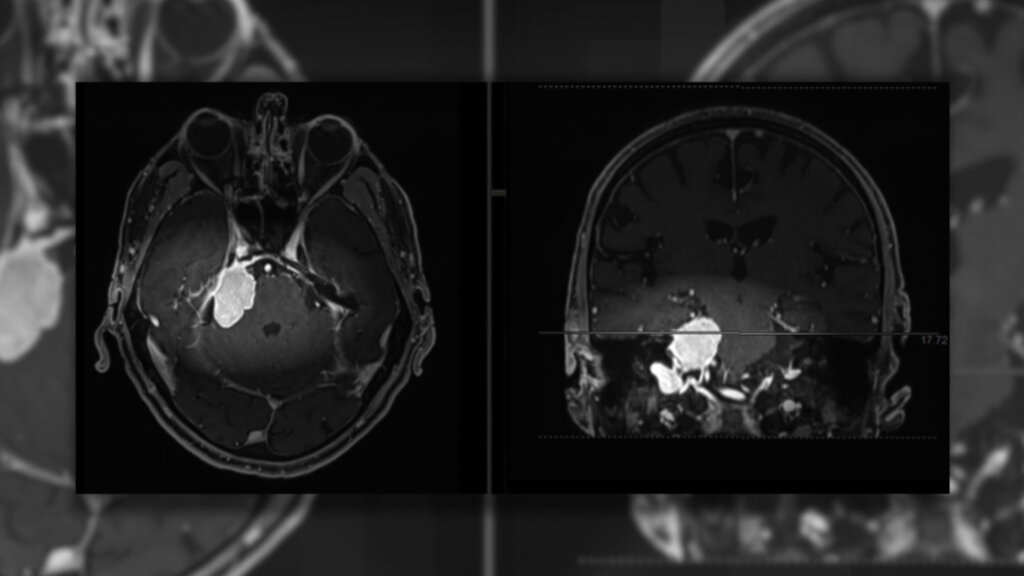

MILANO (ITALPRESS) – I meningiomi sono tumori che originano dalle meningi, le membrane che avvolgono e proteggono il cervello e il midollo spinale. Rappresentano circa il 30% dei tumori cerebrali primitivi e sono tra i più comuni tumori che si sviluppano nella scatola cranica. Nella maggior parte dei casi sono benigni e a crescita lenta, ma in alcune situazioni possono presentare caratteristiche più aggressive. I sintomi variano in base alla posizione e alle dimensioni del tumore e possono includere mal di testa, crisi epilettiche, disturbi visivi, cognitivi o motori. La diagnosi avviene tramite risonanza magnetica con mezzo di contrasto e tomografia computerizzata. La diagnosi e trattamento presso centri specializzati è fondamentale per il miglior esito delle cure. “Un meningioma è una neoplasia che nasce dalle meningi, che non sono altro che l’involucro del cervello e del midollo spinale, quindi del nostro sistema nervoso centrale. È molto importante un messaggio da dare ai pazienti, quando c’è una diagnosi di meningioma non si ha un tumore cerebrale, quindi un tumore che infiltra o cancella la funzione di un’area del cervello: è qualcosa di extracerebrale che lo comprime e, una volta trattato e tenuto sotto controllo, le funzioni vengono ripristinate”, ha detto Federico Pessina, professore ordinario in Neurochirurgia, direttore della scuola di specializzazione in Neurochirurgia di Humanitas University e responsabile dell’unità operativa di Neurochirurgia cranica presso l’istituto clinico Humanitas di Rozzano, in un’intervista per Medicina Top, format tv dell’agenzia di stampa Italpress.